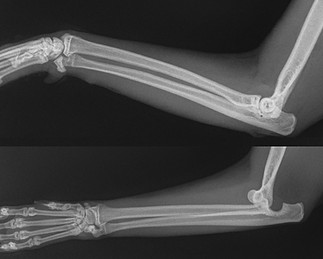

Множественные переломы предплечья

Перелом лучевой и локтевой костей левой и правой лап: многооскольчатый, со смещением, закрытый. Слева - до операции. Справа - на следующий день после операции. Выполнен внеочаговый остеосинтез.

Восстановление опоры: 2 день после операции. Прогноз: благоприятный